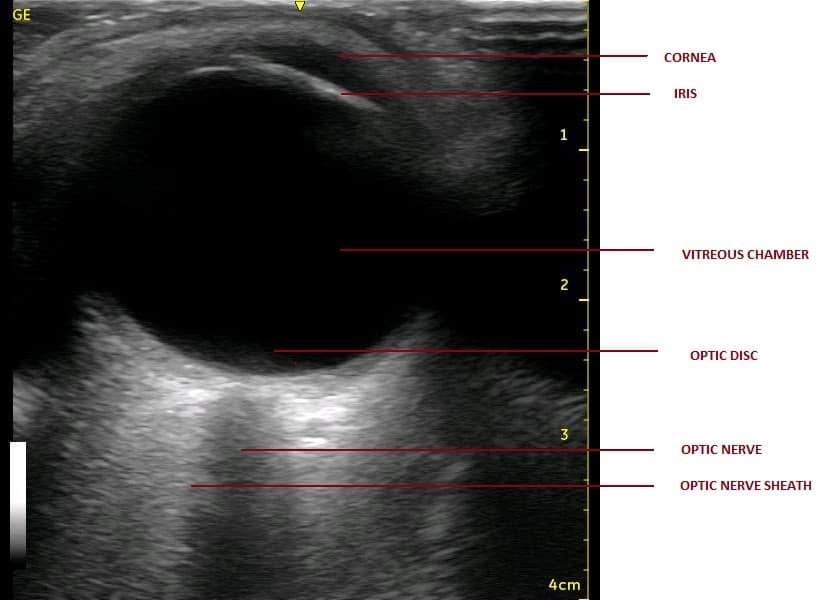

- The following structures are visualised from near to far field (anterior to posterior direction) to gain a proper orientation before proceeding with any measurements (Figures 2 and 3).37

| STRUCTURE | ECHOGENICITY |

| Cornea | Hypoechoic |

| Anterior chamber | Anechoic |

| Lens capsule | Hyperechoic |

| Iris and ciliary body | Hyperechoic |

| Posterior chamber | Anechoic |

| Retina/choroid/sclera (covering layers of eyeball) | Hyperechoic |

| Retro-orbital region (EOM/orbit) | Heterogeneously hyperechoic |

| Optic nerve with its covering sheath | Anechoic linear structure enclosed in hyperechoic sheath (optic nerve sheath) |

Optic nerve is seen as anechoic (black) linear structure bounded by hyperechoic (bright) lines